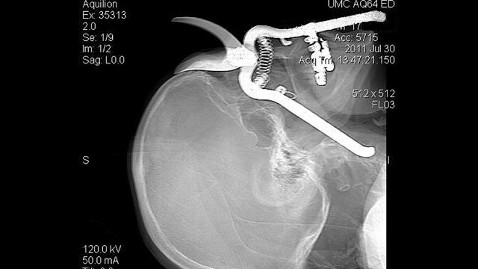

ABC News